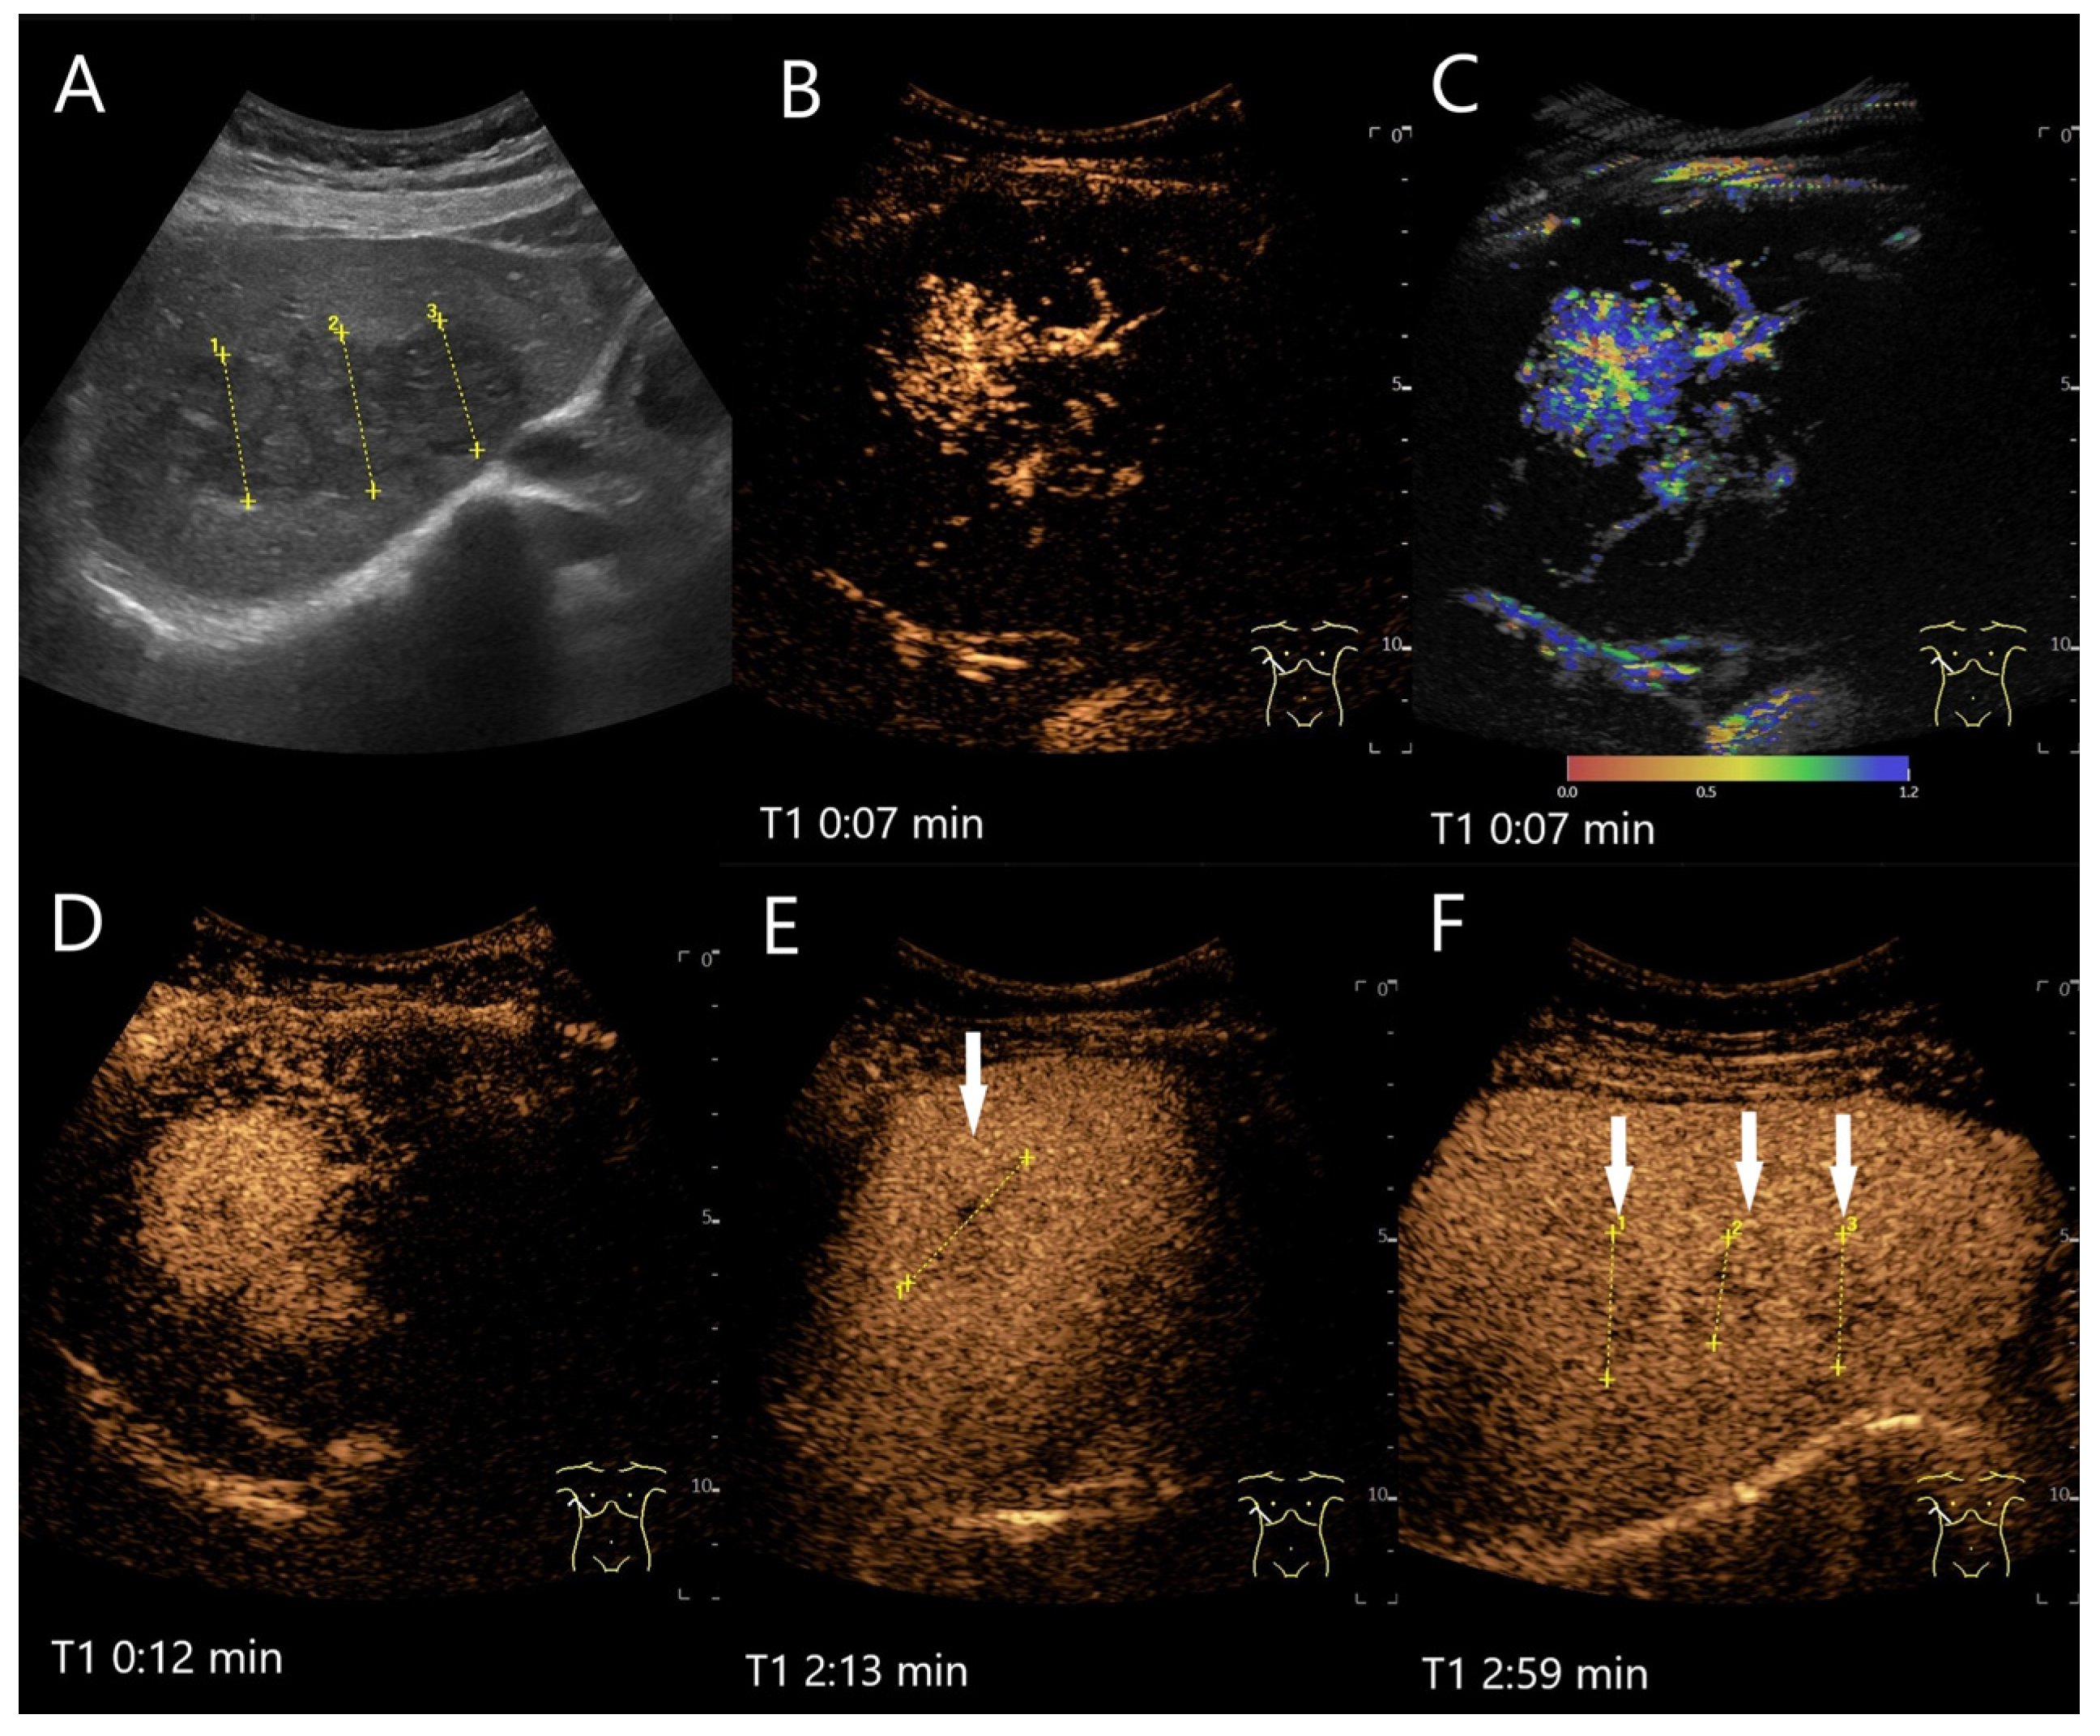

| HCA | Hypo-/iso-/hyperechoic HNF1a HCA (steatotic HCA) are frequently hyperechoic. | centripetal or mixed/diffuse filling. | Iso- or late slight hypoenhancement. Hyperenhancement in some I-HCA. | Absence of portal and central veins. |